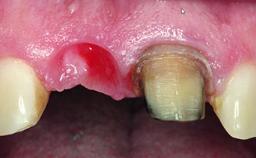

A 15-year-old male patient was referred to us by his pediatric dentist in June 2004 for evaluation of treatment options for his failing tooth 21. The patient had recently seen an endodontist for internal bleaching and been advised that there had been significant resorption and ankylosis. The patient’s mother was concerned because the tooth appeared shorter than the adjacent one. His past dental history was significant for trauma (September 2001), where the tooth had been avulsed and reimplanted. Teeth 11 and 21 had been endodontically treated.

| Bone Volume | Deficient horizontally, requiring prior grafting |